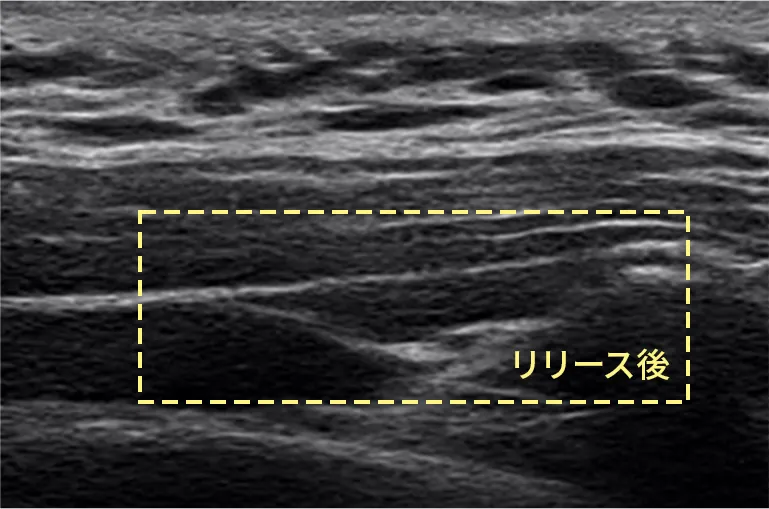

• 筋膜リリース注射前 筋膜リリース注射前のエコー写真

• 筋膜リリース注射後 筋膜リリース注射後のエコー写真

当院では肩こりの原因に直接アプローチできる注射による筋膜リリース(ハイドロリリース)を行っています。超音波装置を使用して、実際に筋膜が剥がれていく様子を目で見て確認しながら治療をします。この直達的な手技により マッサージでは行えない筋膜リリースが可能です。

そこで、 エコーを見ながら針と液体(生理的食塩水)を用いて、直接的に膜を剥がしていくのです。これを筋膜リリース(ハイドロリリース)注射と呼びます。